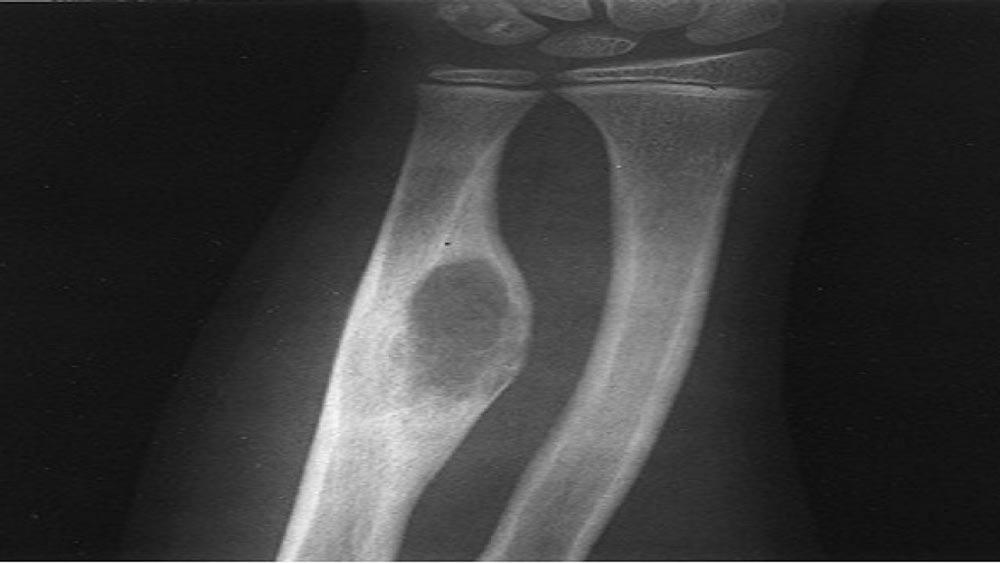

Chụp X-quang bác sĩ thường có thể phát hiện tổn thương xương do ung thư hoặc xương mới phát triển do ung thư. Họ cũng có thể xác định các triệu chứng của bạn có phải do nguyên nhân khác chẳng hạn như gãy xương (gãy xương).

U xương là loại ung thư xương dễ mắc nhất. U xương thường xảy ra ở trẻ em và thanh thiếu niên, nó bắt đầu từ trong xương của chân hoặc cánh tay. Trong một số trường hợp hiếm, u xương có thể phát sinh bên ngoài xương (u xương ngoài xương).